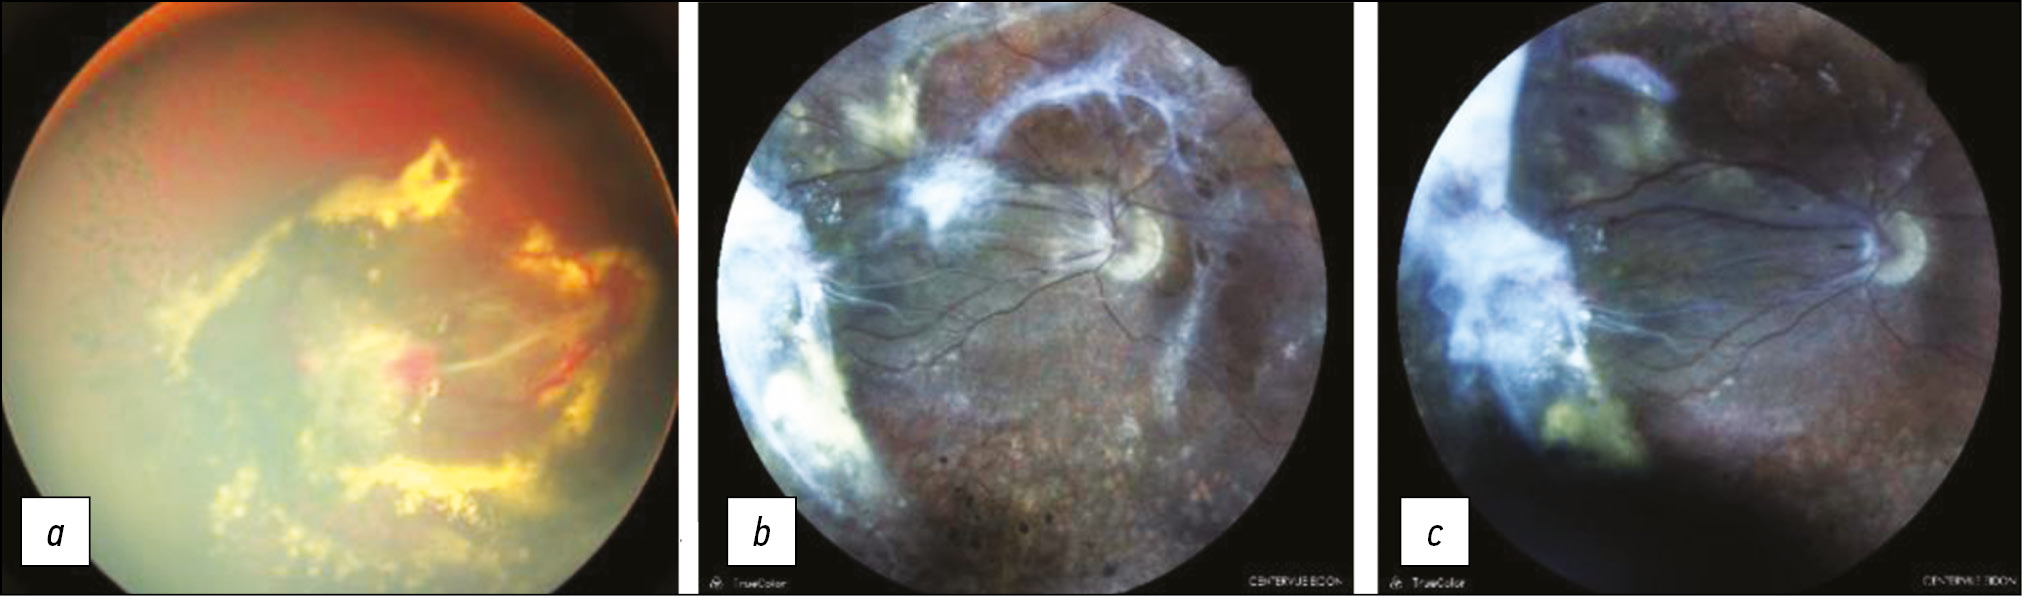

В результате вмешательства в одном случае достигнуто полное прилегание сетчатки, в 6 глазах отмечено снижение тракции с уменьшением высоты складки/отслойки (рис. 5). МКОЗ повысилась в одном глазу и не изменилась в 6 глазах.

Рис. 5. Пациентка К., семейная экссудативная витреоретинопатия стадии 4А. фотография глазного дна: а, b — до операции, эпиретинальный фиброз, складка сетчатки от диска зрительного нерва к височной периферии, максимальная корригированная острота зрения (МКОЗ) 0,02; c — после операции, уменьшение тракции в области заднего полюса, высоты складки, МКОЗ 0,01.

Под наблюдением в сроки от 6 месяцев до 5 лет (медиана 2,5 года) находились 8 пациентов. В двух глазах через 3–4 месяца выявлен рецидив ОС, обусловленный нарастанием субретинальной экссудации в одном глазу и формированием вторичного разрыва — в другом. В первом случае проведено дренирование субретинальной жидкости без значительного эффекта. Во втором случае после локального эписклерального пломбирования и двухкратной ревизии витреальной полости достигнуто неполное прилегание сетчатки. В одном глазу через 3 года выявлена репролиферация с нарастанием тракции сетчатки, была выполнена повторная витректомия с устранением тракции и стабилизацией в течение одного года наблюдения (рис. 6). В трёх глазах с эндотампонадой силиконовым маслом через 2 месяца–2 года 9 месяцев после вмешательства проведена микроинвазивная экстракция катаракты с имплантацией ИОЛ.

Рис. 6. Пациент Р., семейная экссудативная витреоретинопатия стадии 4Б, фотография глазного дна: a — до операции. эпиретинальный фиброз и субретинальный экссудат; b — через 3 года после операции, эпиретинальная репролиферация; максимальная корригированная острота зрения (МКОЗ) 0,05; c — после повторного вмешательства, снижение тракции, МКОЗ 0,05.

В 5-й стадии хирургическое лечение проведено в 3 глазах из 8 (37,5%). В двух случаях в связи с развитием синдрома мелкой передней камеры выполнена ленсвитрэктомия с устранением иридокорнеального контакта и органосохранным эффектом. В одном глазу с открытой воронкообразной ОС выполнена микроинвазивная витрэктомия с эндотампонадой силиконовым маслом. Отмечалось повышение остроты зрения со светопроекции до 0,05, однако, через 1,5 года диагностирован рецидив ОС со вторичным разрывом. Повторное хирургическое вмешательство было неэффективно.